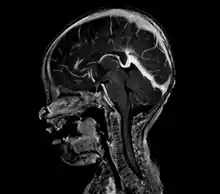

A cerebral AVM diagnosis is established by neuroimaging studies after a complete neurological and physical examination.[5][12] Three main techniques are used to visualize the brain and search for an AVM: computed tomography (CT), magnetic resonance imaging (MRI), and cerebral angiography.[12] A CT scan of the head is usually performed first when the subject is symptomatic. It can suggest the approximate site of the bleed.[3] MRI is more sensitive than CT in the diagnosis, and provides better information about the exact location of the malformation.[12] More detailed pictures of the tangle of blood vessels that compose an AVM can be obtained by using radioactive agents injected into the blood stream. If a CT is used in conjunctiangiogram, this is called a computerized tomography angiogram; while, if MRI is used it is called magnetic resonance angiogram.[3][12] The best images of a cerebral AVM are obtained through cerebral angiography. This procedure involves using a catheter, threaded through an artery up to the head, to deliver a contrast agent into the AVM. As the contrast agent flows through the AVM structure, a sequence of X-ray images are obtained.[12]